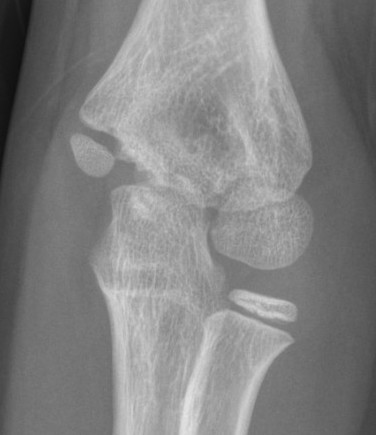

X-ray

Undisplaced

- typically metaphyseal flake

- looks minimally displaced on AP and lateral

- perform an internal oblique x-ray to exclude displacement

Displaced

Injured left elbow v injury right elbow